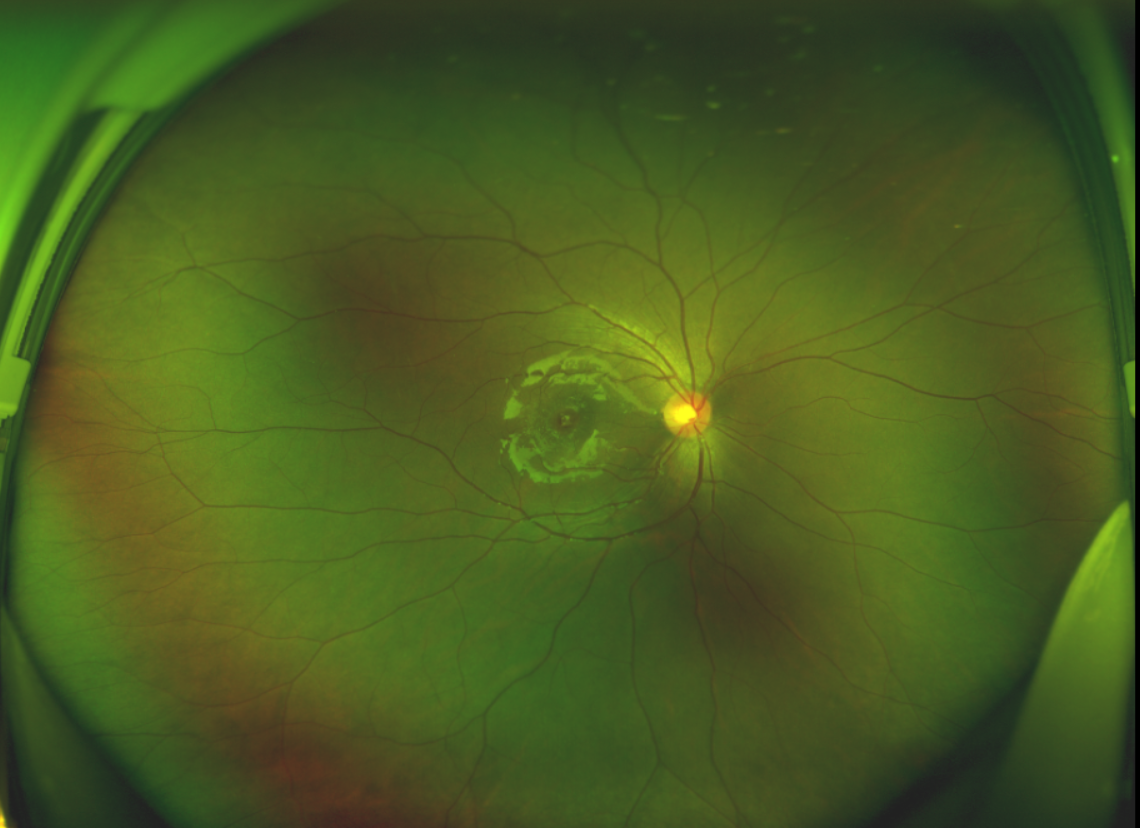

黃斑位于視網(wǎng)膜正中心,是視覺最敏銳的區(qū)域,堪稱“眼底的心臟”,負(fù)責(zé)我們閱讀、駕駛、識(shí)別人臉等精細(xì)視覺。 當(dāng)黃斑區(qū)的神經(jīng)組織出現(xiàn)全層缺損,形成一個(gè)“孔洞”,即為黃斑裂孔,它會(huì)直接導(dǎo)致中心視力急劇下降、視物變形、視野中心出現(xiàn)暗區(qū)。

經(jīng)過詳細(xì)的檢查和評(píng)估,王曉波主任決定采用“內(nèi)界膜翻轉(zhuǎn)覆蓋聯(lián)合粘彈劑固定術(shù)”為誠誠進(jìn)行治療。

術(shù)中,醫(yī)生精細(xì)剝離黃斑區(qū)的內(nèi)界膜后,并非直接丟棄,而是巧妙地給它翻個(gè)面,讓它變成一塊天然“創(chuàng)可貼”,嚴(yán)密覆蓋在黃斑裂孔的表面。覆蓋的內(nèi)界膜像微型支架一樣撐住裂孔邊緣,防止它擴(kuò)大;同時(shí),這層膜本身含有能促進(jìn)生長(zhǎng)的“養(yǎng)分”,能顯著刺激裂孔周圍的視網(wǎng)膜組織像爬山虎一樣快速生長(zhǎng)、蔓延過來,最終把裂孔“補(bǔ)”好。

除此之外,利用自體組織覆蓋為黃斑裂孔提供了理想的愈合環(huán)境,裂孔閉合速度顯著快于傳統(tǒng)方法。誠誠接受手術(shù)24小時(shí)后,檢查可見內(nèi)界膜瓣位置良好;術(shù)后1個(gè)月,黃斑裂孔已經(jīng)閉合,視力恢復(fù)到0.5;術(shù)后兩個(gè)月,視力進(jìn)一步提升到0.7。